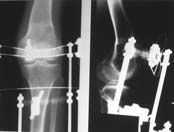

> Пациент В. 53 лет, травма в феврале 2009. ДЗ. Открытый оскольчатый перелом нижней трети голени. При боли поступлении выполено ПХО, аппарат Илизарова. В последующем проводили ВХО, резекция костных отломков, укорочение 6 см, рана зажила. Была выполнена остеотомия большеберцовой кости в проксимальном отделе, резекция. Производилось тракция.

> На последних рентгенограммах выявлено, что одновременно с "выращиванием" регенерата произошло низведение надколенника  на длину выращенного регенерата.

> Клинически: активное разгибание сохранено, объем движений в колене 180-110 градусов.  Черными стрелками обозначен верхний край надколенника с одной и с другой стороны. Красная стрелка обозначает пальпируемую связку надколенника.

> Причина - остеотомия выше места прикрепления связки надколенника.